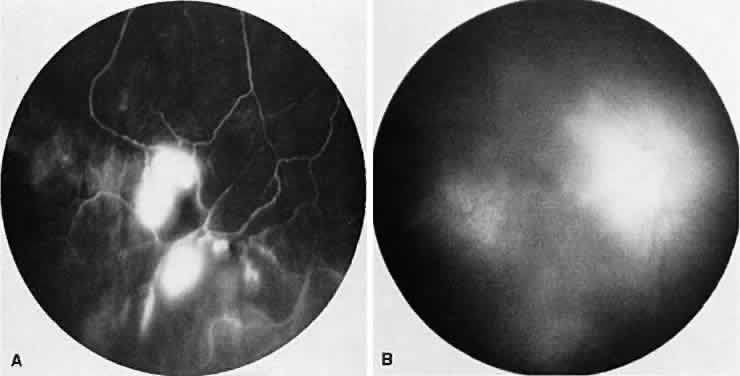

Vogt-Koyanagi-Harada syndrome, also known as uveomeningoencephalitis syndrome, is a systemic disease often found in young, darkly pigmented whites, blacks, native Indians, Hispanics, and Asians. It presents as an anterior and posterior uveitis with disc hyperemia, disc edema, and exudative retinal detachment (Figs. 2A and B and 3A). Systemic signs and symptoms include headache, hearing loss, poliosis, vitiligo, nuchal rigidity, seizures, and even coma. SRNV and disciform scars are late complications. The differential diagnosis should include AMPPPE and sympathetic ophthalmia.

Fig. 2. Vogt-Koyanagi-Harada syndrome. (A) Fundus photograph of the right eye and (B) the left eye showing bullous retinal detachments. (C) Fluorescein angiogram showing multiple hyperfluorescent leaks at the level of the retinal pigment epithelium. (D) Multiple coalescing leaks and fluorescein staining of the subretinal fluid. Large areas of hyperfluorescence involving the entire right posterior pole due to pooling of dye beneath the subretinal space.

Fig. 3. Vogt-Koyanagi-Harada syndrome. A. Fundus photograph of the left eye showing multifocal serous retinal detachment. B. Late fluorescein angiogram showing pooling of dye in the areas of serous detachment. C. Indocyanine angiography showing areas of blocked fluorescence corresponding to serous detachment. More areas of hypofluorescence are noted than those observed on fluorescein angiogram.

There is a characteristic fluorescein angiographic appearance in the early phase showing multiple discrete hyperfluorescent dots at the retinal pigment epithelial level that enlarge over time (see Fig. 2C and D). In the late phase, if there is a serous detachment, the fluorescein pools beneath the subretinal space (see Fig. 3B). The edematous disc hyperfluoresces in the late phase. Generally, the retinal vessels are unaffected.7,8 Retinochoroidal anastomoses also have been documented by fluorescein angiography.9

ICG angiography shows multiple hypofluorescent spots in the posterior pole (see Fig. 3C). These spots may coalesce and obscure the filling of large choroidal vessels. When serous retinal detachment develops, the marked hyperfluorescence observed on FA is not as prominently noted in ICG angiography, presumably because of the highly protein-bound nature of ICG. In fact, diffuse late hypofluorescence may be observed in patients with serous retinal detachment.10 Ill-defined areas of hyperfluorescence corresponding to diffuse choroidal staining may be seen in some cases in the late phases of the angiogram. The optic disc may stain with ICG in the acute phase but usually is minimal compared to that observed on FA.